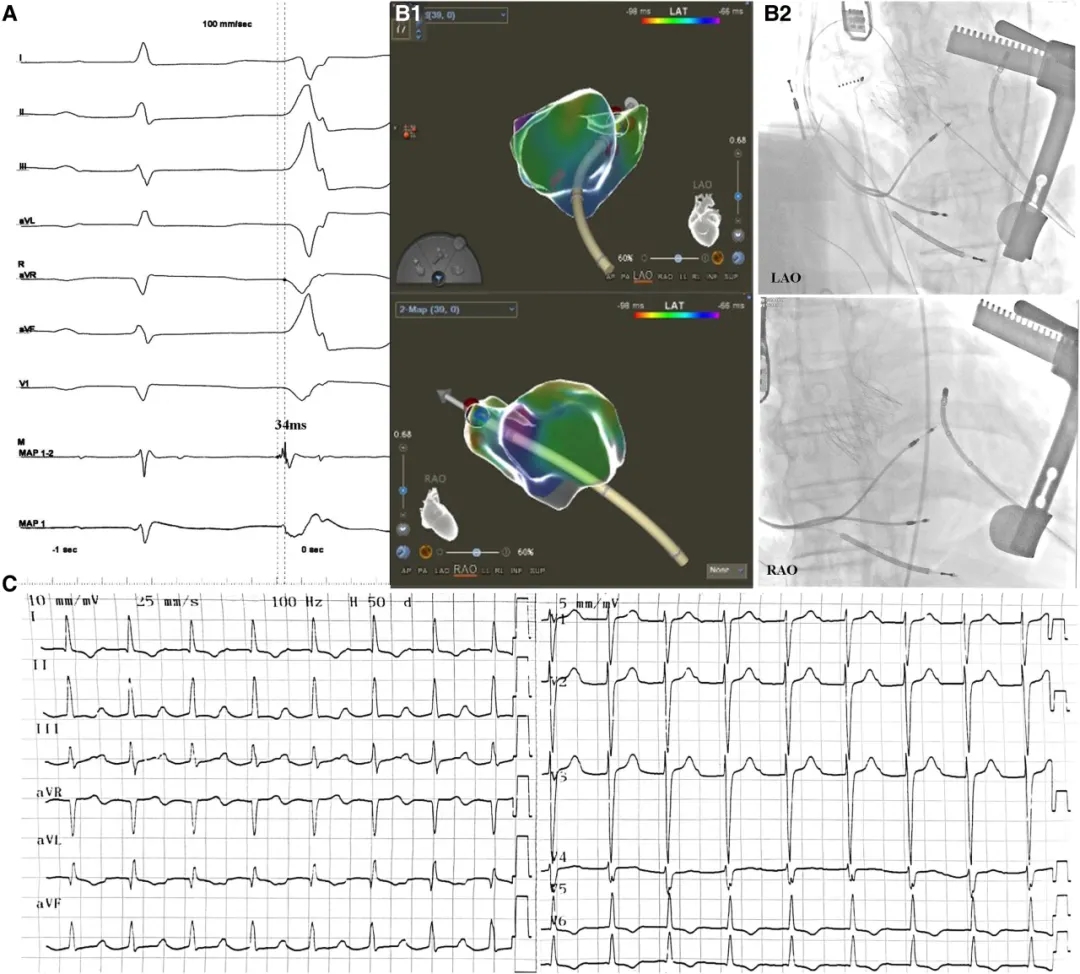

随后经同一心尖穿刺点置入短鞘,导入消融导管,在三维心脏电生理标测系统引导下于二尖瓣环1点钟位置标测到室性早搏起源点,其局部电位较体表心电图提前34ms。射频消融(接触力8-12克,功率35W,温度43℃,灌注流速15mL/min)3秒内成功消除室性早搏,并于相邻位点进行巩固消融(图2)。

图2 消融靶点。(A) 室性早搏(PVC)起源点的心内电生理特征:最早激动点较体表心电图提前34 ms,消融导管(MAP1-2)可记录到心房电位。(B) 消融靶点的三维影像(B1)与X光投照体位(B2)。(C) 术后心电图。RAO:右前斜位,LAO:左前斜位。